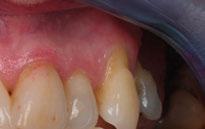

Acude a la consulta un paciente masculino de 35 años exigiendo cambios en la estética de sus dientes. El examen intraoral clínico y fotográfico reveló pérdida de estructura dentaria con facetas de desgaste en dientes anterosuperiores e inferiores, acentuándose hacia zonas oclusales de dientes posteriores.

El diagnóstico evidenció que el paciente presentaba alteración en la dinámica de la guía anterior por el desgaste de los bordes incisales, con pérdida de dimensión vertical oclusal (VDO), alteración del plano de oclusión y relaciones interoclusales inestables (Figuras 1 y 2)

Se obtuvieron modelos de estudio (Figuras 3-6) digitales mediante un escáner confocal de luz azul estructurada (PrimeScan, Dentsply Sirona) y se planificó un protocolo de desgaste mínimamente necesario y conservador de las estructuras